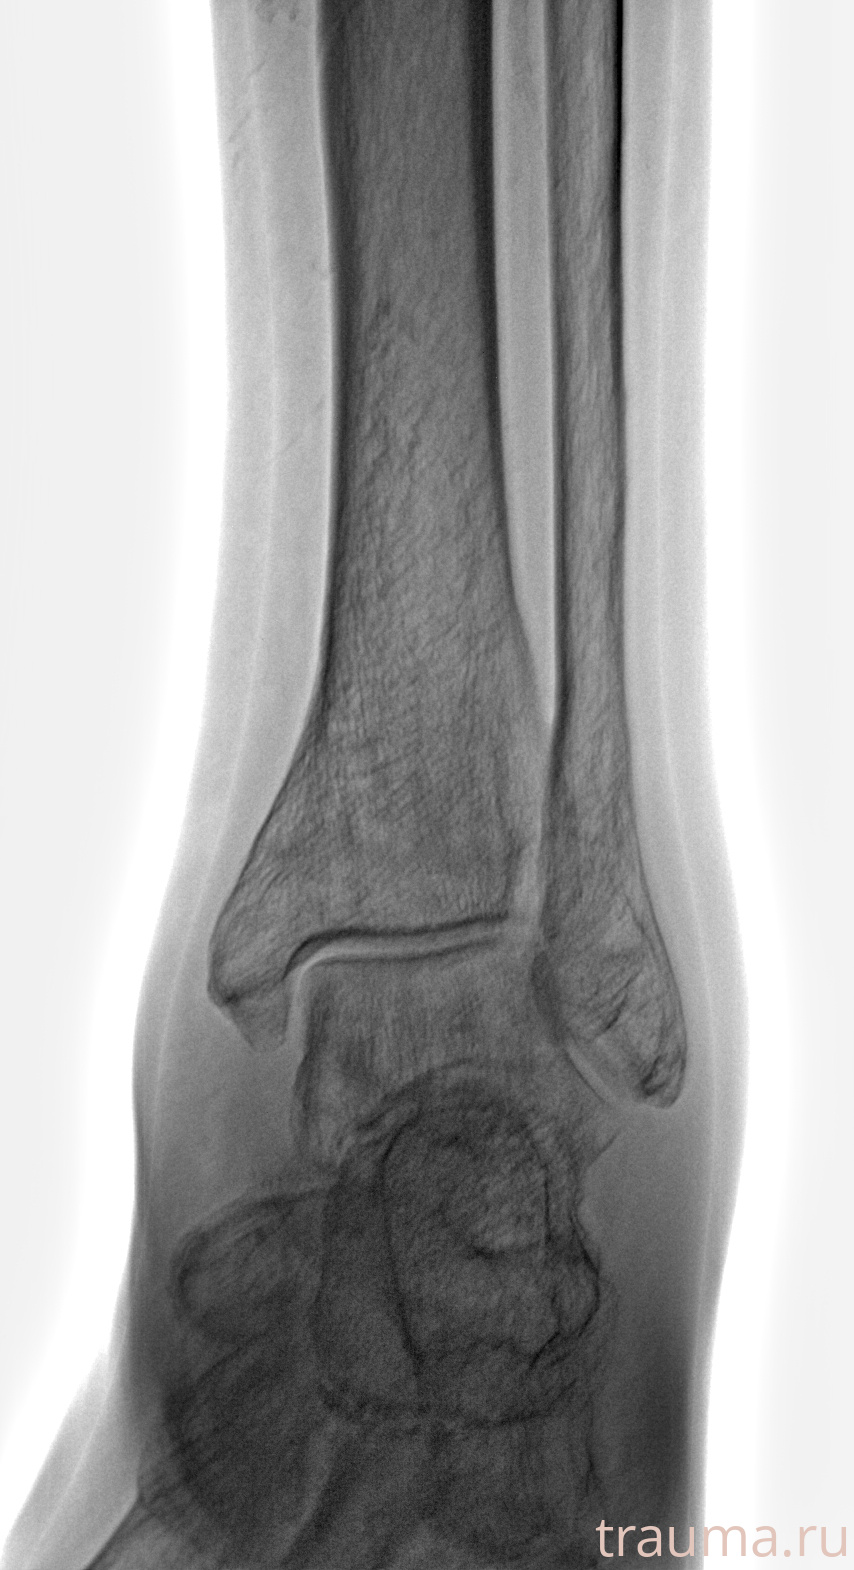

Рентгенограммы

Рентген на дому: по вашему адресу приезжает врач-рентгенолог, травматолог-ортопед с мобильным рентгеновским аппаратом, проводит диагностику травмы или заболевания, делает необходимые рентгенограммы, дает рекомендации по дальнейшему лечению. Получить качественные снимки в домашних условиях возможно благодаря уникальной методике, разработанной МосРентген Центром для института  Склифосовского